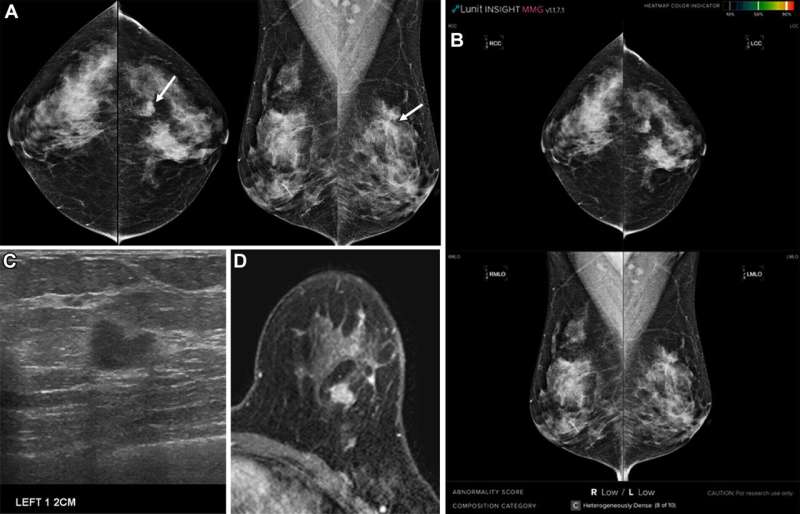

Исследователи из Центра маммологии Медицинского колледжа Корейского университета — профессор Сонг Сонг Сонг (отделение радиологии, больница Анам Корейского университета) и профессор Окхи У (отделение радиологии, больница Гуро Корейского университета) — проанализировали 1097 случаев рака молочной железы, диагностированных в период с 2014 по 2020 год, с помощью коммерческой корейской программы искусственного интеллекта (Lunit Insight MMG).

ИИ пропустил 17,2% случаев рака люминального типа, 14,5% случаев трижды негативного рака и 9% случаев HER2-позитивного рака. Пропущенные инвазивные раки, как правило, встречались у молодых женщин , имели размер опухоли не более 2 см, более низкую гистологическую степень злокачественности, меньшее количество метастазов в лимфатические узлы, низкую экспрессию Ki-67, локализовались вне железистых областей и часто относились к категории 4 по BI-RADS. Наиболее частыми причинами пропуска были плотная ткань молочной железы, негаландулярное расположение опухоли, структурные искажения и микрокальцификаты. Примечательно, что 61,7% этих видов рака были признаны рентгенологами обнаруживаемыми.